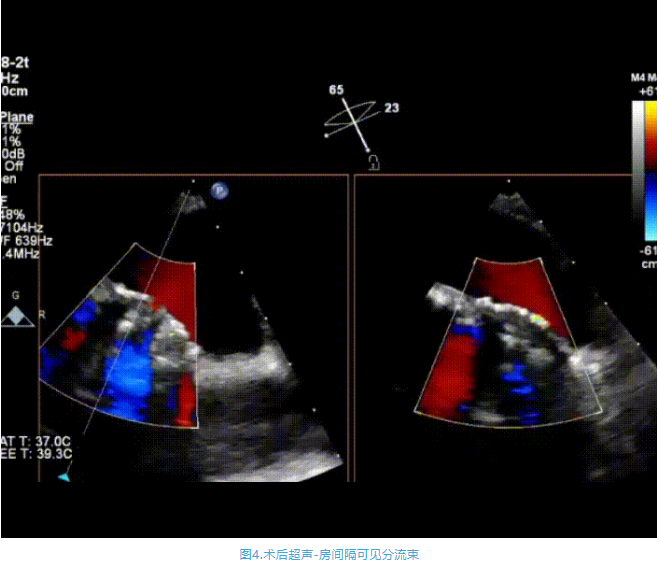

術(shù)中首先在局麻下穿刺股動脈、股靜脈,完成心導管檢查評估后轉(zhuǎn)為全麻,在食道超聲引導下穿刺房間隔,穿刺成功后將加硬導絲送入左上肺靜脈建立軌道,根據(jù)患者病情行球囊預擴張后植入6mm孔徑房間隔造孔支架,經(jīng)透視及食道超聲評估支架左右盤展開良好,夾持于房間隔兩側(cè),固定穩(wěn)定、位置良好,食道彩超顯示房水平右向左為主分流,分流孔直徑符合預期大小,心導管檢查評估達到預期效果,釋放造孔支架。術(shù)后12h患者下床活動,恢復順利,擬于近日完善術(shù)后評估后出院。

心房分流術(shù)是通過器械制造穩(wěn)定可控的心房間分流,適應證包括藥物治療效果不佳的左心衰或肺動脈高壓右心衰。本例患者為肺動脈高壓右心衰,術(shù)中成功放置MicroFlux®造孔支架在房間隔理想位置上,創(chuàng)造穩(wěn)定可控的心房間分流(此例患者以右向左分流為主),在不顯著增加左心負擔的情況下,有效降低患者右心房壓力、緩解體循環(huán)淤血,增加左心輸出量,改善患者癥狀、活動耐力和生存質(zhì)量。同時,國內(nèi)外也已經(jīng)開展多項房間隔造孔支架在射血分數(shù)保留、射血分數(shù)中間值和射血分數(shù)降低的左心衰患者中的臨床研究,結(jié)果顯示對于經(jīng)過充分的規(guī)范化藥物治療后仍控制不佳的患者,心房分流術(shù)可改善患者的癥狀及生存質(zhì)量。